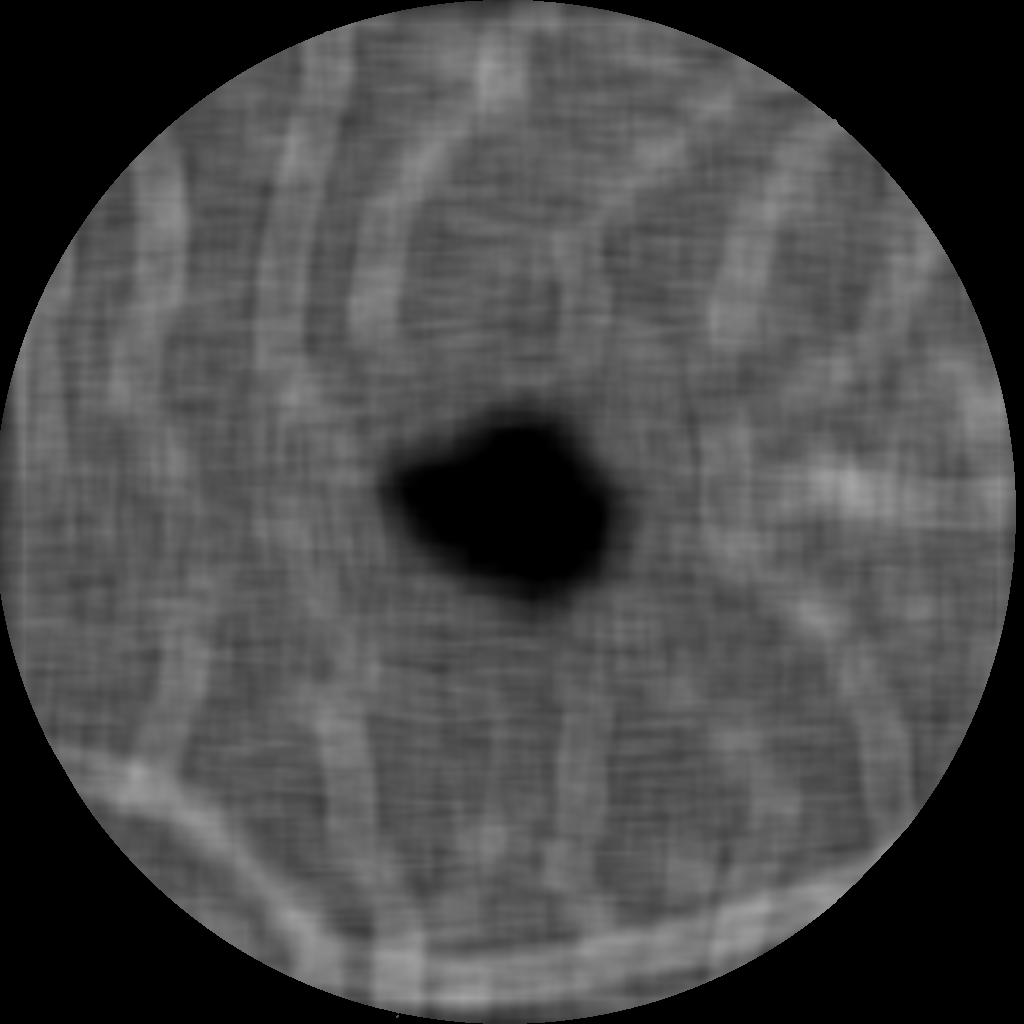

for some chosen frequency ω𝜔\omega, orientation θ𝜃\theta and σ1subscript𝜎1\sigma_{1}, σ2subscript𝜎2\sigma_{2} correspond to the spatial widths of the filter, which is then applied to an image. Here, we choose the parameters as suggested in [19] and use 333 frequency scalings {ωi}i=13superscriptsubscriptsubscript𝜔𝑖𝑖13\{\omega_{i}\}_{i=1}^{3} and 666 orientations {θj}j=16superscriptsubscriptsubscript𝜃𝑗𝑗16\{\theta_{j}\}_{j=1}^{6} to create our Gabor filter bank. The 36=1836183\cdot 6=18 computed Gabor filters are then convolved with the original image Im×n𝐼superscript𝑚𝑛I\in\mathbb{R}^{m\times n} to derive the new image representations in m×nsuperscript𝑚𝑛\mathbb{R}^{m\times n}. Next, for fixed ωisubscript𝜔𝑖\omega_{i}, we take the pixel-wise maximum in the images corresponding to the 666 orientations {θj}j=16superscriptsubscriptsubscript𝜃𝑗𝑗16\{\theta_{j}\}_{j=1}^{6}, leading to 333 images I1,I2,I3subscript𝐼1subscript𝐼2subscript𝐼3I_{1},I_{2},I_{3} with different emphasized frequency ranges, see Figure 1. These new representations are our basis for the further processing.

Refer to caption

(a) I1subscript𝐼1I_{1}: High frequencies

(b) I2subscript𝐼2I_{2}: Medium frequencies

(c) I3subscript𝐼3I_{3}: Low frequencies

Figure 1: New image representations are obtained by the convolution of the original image I𝐼I with Gabor filters. The images I1,I2,I3subscript𝐼1subscript𝐼2subscript𝐼3I_{1},I_{2},I_{3} correspond to the 333 chosen frequency ranges defined by {ωi}i=13superscriptsubscriptsubscript𝜔𝑖𝑖13\{\omega_{i}\}_{i=1}^{3}.

For the image processing steps that focus on the identification of the small and big vessels, we will use the image representation I2subscript𝐼2I_{2} that emphasizes the medium frequencies. These frequencies correspond best to the vessels we aim to identify and therefore the new representation reveals a more clear structure of the relevant characteristics. We smooth the image I2subscript𝐼2I_{2} by convolution with a Gaussian filter